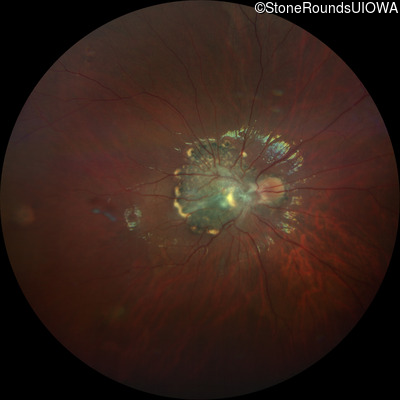

This 9 year old male was noted to have some crossing of his eyes at 2 months of age and the eye exam which followed identified a retinal lesion in the right eye. When he was six years old an epiretinal membrane was noted in his left eye. Two years later it was decided that it was a thin hamartoma in that eye as well. He underwent neuroimaging at age 7 which identified bilateral acoustic neuromas.